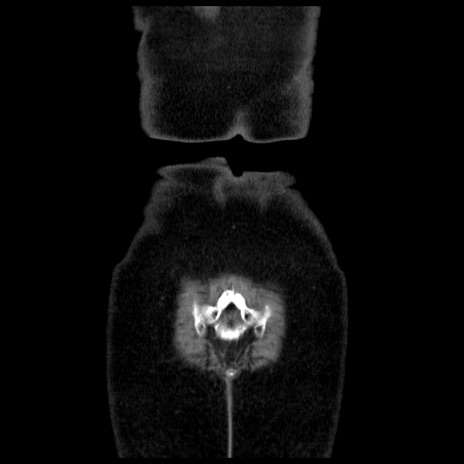

症例13(冠状断像)

症例